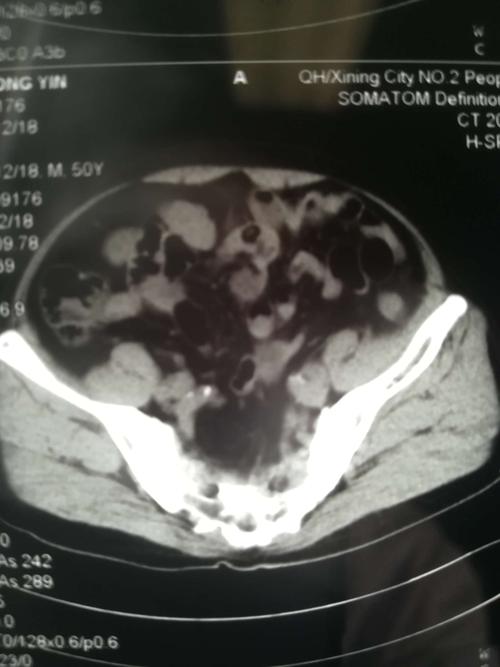

患者中老年男性,诊断:左侧腰疝